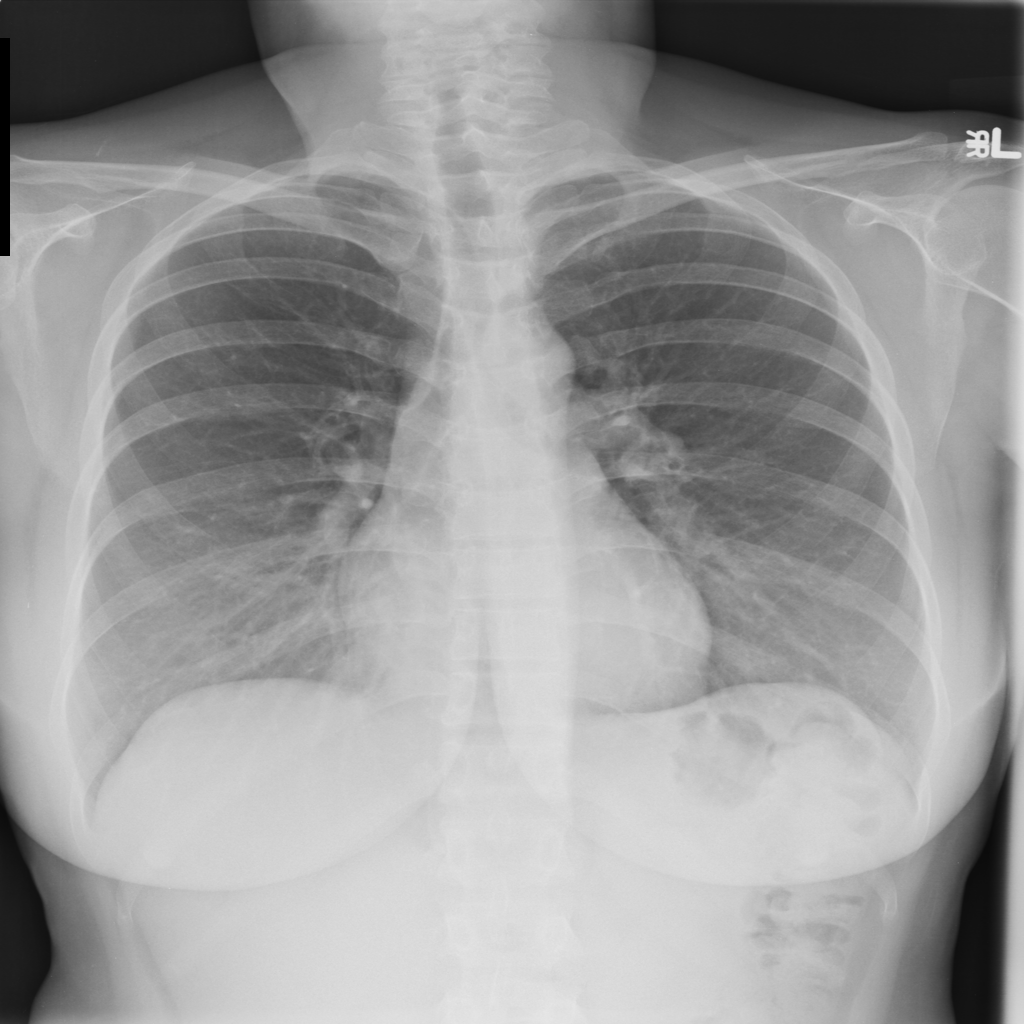

PAT-EBE1 · IMG-019Pneumonia

PAT-EBE1 · IMG-019

AP